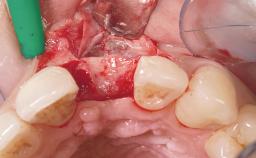

Immediate Flapless Placement of an Implant in a Maxillary Right Lateral Incisor Site

This 43-year-old male patient, a non-smoker, came to our practice because of a fracture of tooth 12 caused by a bicycle accident. Due to the combined para- and infrabony crown and root fracture, tooth extraction, and subsequent implant placement were suggested to the patient as the therapy of choice. The patient had high esthetic expectations with regard to the treatment outcome and asked for an immediate fixed provisional restoration. His individual esthetic risk profile summed up to a medium esthetic risk.

Abutment Type CAD/CAM

Prosthesis Type FDP

Loading Protocol Immediate